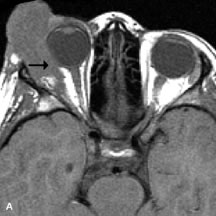

Dermoid cysts appear as rounded, well-defined lesions typically contiguous with an orbital bony suture. The high-intensity signal on T1-weighted images is attributed to the sebaceous-produced lipid contents (Fig. 18).31,50 Mucoceles may demonstrate a hypointense or hyperintense signal on MR images, depending on the concentration of proteinaceous or inflammatory fluid components. The integrity of the bony walls of the expanded sinus cavities cannot be assessed on MR as well as by CT.37,50,55,56 A high-signal intensity on Tl- and T2-weighted images is characteristic of orbital chronic hematic cysts because of the blood-breakdown products within the cysts.57

Fig. 18. A. T1-weighted, (B) T2-weighted fat-suppressed, and (C) T1-weighted fat-suppressed MR scans demonstrate a small dermoid cyst arising near the palpebral portion of the lacrinal gland (arrows). The lesion is similar in signal intensity to fat on the T1-weighted scan (A) consistent with a high adipose tissue content. The lesion shows fat-suppression and low signal intensity on the two fat-suppressed sequences (B and C) confirming its high lipid content.